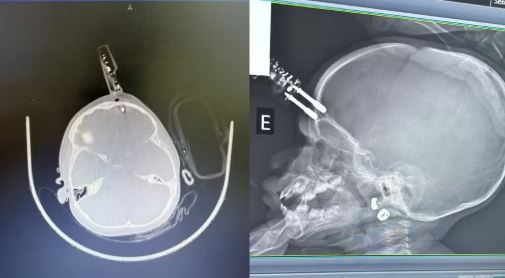

Uma bebê de apenas 1 ano precisou passar por cirurgia de emergência após sofrer um grave acidente doméstico na última terça-feira (13). A criança caiu da cama segurando um carregador de celular, que acabou perfurando a região frontal da testa.

A principal hipótese médica aponta que a bebê estava com o carregador na mão no momento em que caiu. Durante a queda, o objeto atingiu a cabeça de forma direta e acabou penetrando a testa, próximo à região dos olhos.

A equipe médica realizou a retirada do objeto, limpeza profunda da ferida, lavagem cirúrgica e reconstrução da área afetada.